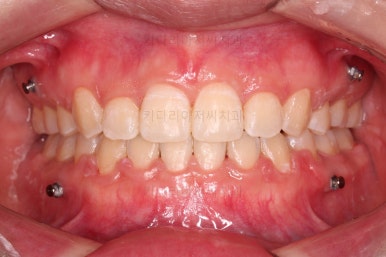

초진 시 입안의 모습이에요. 치열이 많이 나쁜 편은 아니고 앞니쪽이 조금 삐뚤어져 있네요.

특히 윗니 작은 앞니 하나가 아랫니보다 안으로 쑥 들어가 있어서 옆에 있는 송곳니가 덧니처럼 보여요.

라고 대부분 말씀 들을 하시지만 실제로 입 안을 보면 송곳니(덧니)가 많이 튀어나가 있기 보다는 옆에 있는 작은 앞니가 쏙 들어가서 상대적으로 튀어나와 보이는 경우가 대부분이에요.

이래나 저래나 덧니처럼 보이는 건 마찬가지이고, 공간을 확보하여 가지런하게 해줘야 하는 것도 사실이지만요.